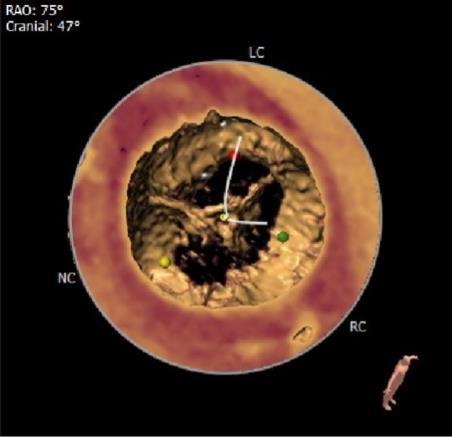

钙化分布:

主动脉根部CT动态图: